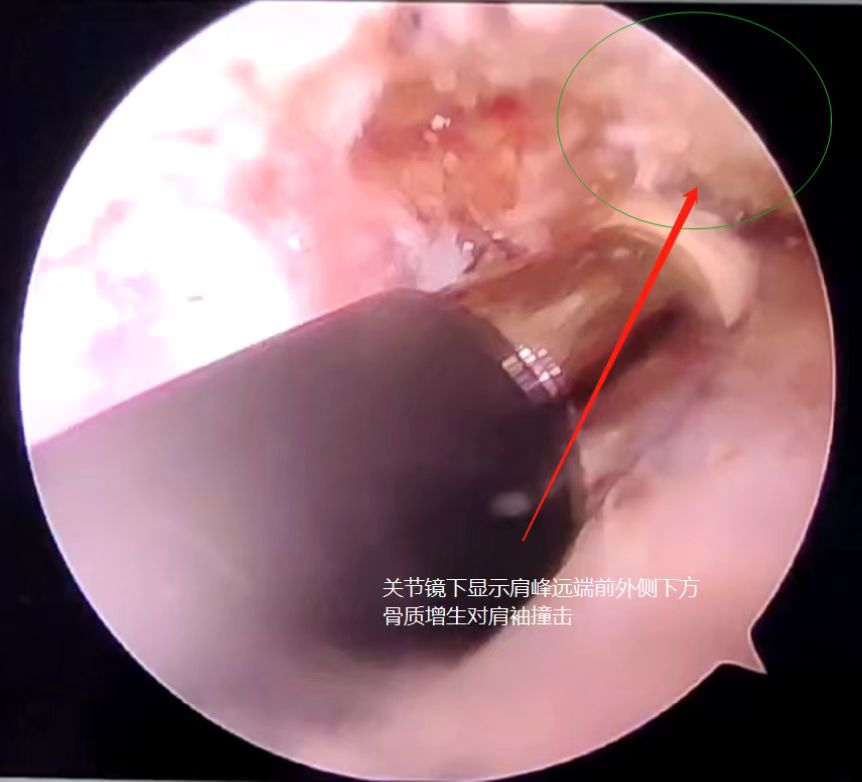

术中予肩关节粘连松解及肩峰下成形,肩袖局部撕裂予缝合一针

针对患者的病情,唐国华主任医师精心设计手术方案,充分进行术前准备,带领骨科团队为患者行全麻下经关节镜辅助下右肩峰下成形+关节囊松解+肩袖缝合术。